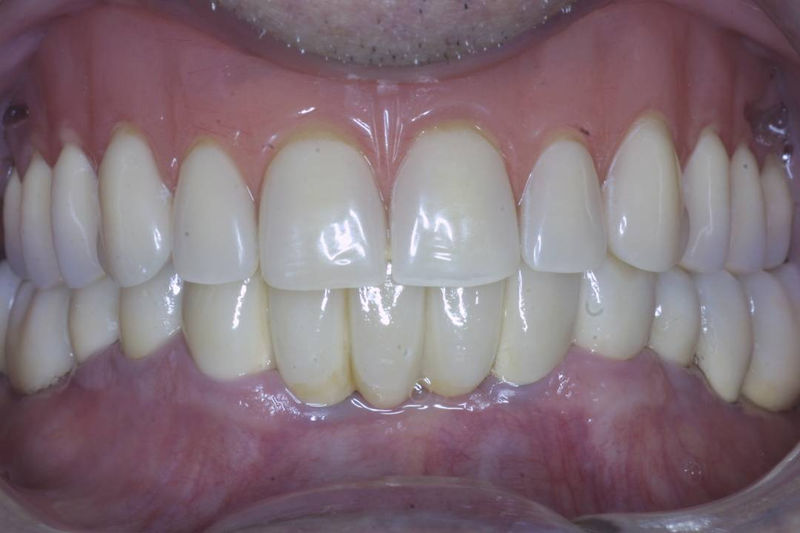

Implante fracasado, extracción, carillas, coronas y prótesis fija.